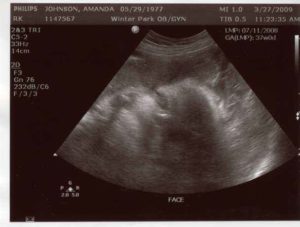

Чтобы исключить такое состояние, даже после получения положительного результата теста на беременности, стоит записаться на ультразвуковое исследование. Обычно оно проводится вагинально при помощи специального датчика.

Но так как многие женщины бояться, что такое обследование вызовет выкидыш, можно записаться на УЗИ на полный мочевой пузырь.

В таком случае врач-узист сделает процедуру абдоминально, что означает проведение процедуры на поверхности живота при помощи небольшого датчика и специального геля.